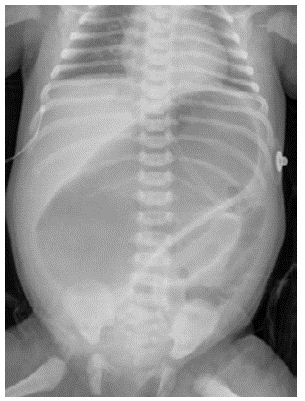

Invasive ventilation was initiated and a nasogastric tube was passed in-situ. An abdominal x-ray showed a large dilated loop of bowel (Figure 2), without a double bubble sign, ruling out duodenal atresia. Based on those findings, in her third day of life, an exploratory laparotomy was performed. A right colon atresia type III (Grosfeld classification) 11 was identified, with a difference of proximal distal caliber from 10 to 1 (Figure 3). A derivative Hartmann's colostomy was performed, given the difference of caliber size that did not allow primary anastomosis. Rectal biopsies were taken, reporting ganglion cells and ruling out Hirschsprung's disease.

3A. Colon atresia type III.

Figure 3: 3A. Colon atresia type III.

Source: Own elaboration based on the data obtained in the study.

3B. Evidence of difference in approximate distal 10-1 caliber. (*) Distal, (Arrow) Proximal.

Figure 3: 3B. Evidence of difference in approximate distal 10-1 caliber. (*) Distal, (Arrow) Proximal.